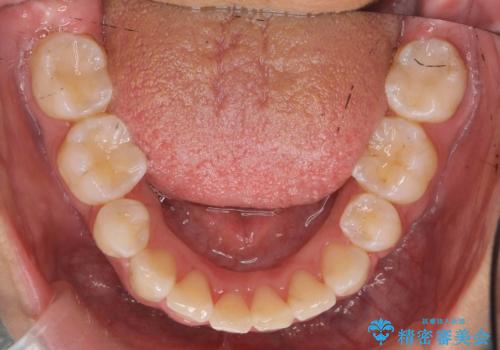

前歯のがたがた 前歯が内側に傾いている

- 前歯のがたがたを主訴に来院。

上の歯並びが前にずれて、さらに前歯が内側に倒れて過蓋咬合を呈していました。